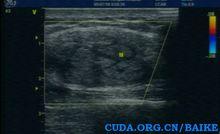

病變的肌層內部回聲呈"地圖版塊樣"不均質混合回聲,高回聲內相間條狀低回聲,內見血流信號,但可見相對正常的肌束。

患者,男,59歲,自覺右側腰背部有一包塊,彩超見右側背部腋後線肌層見大小為3.11*1.73cm的梭形稍強回聲,內見無回聲,呈“地圖版塊”征,可見點狀血流信號。